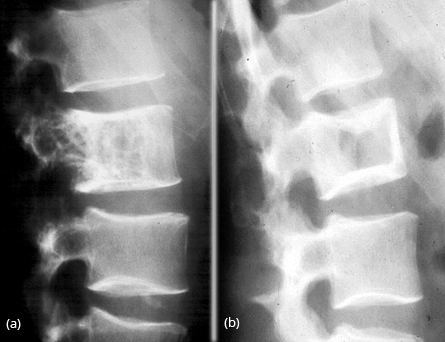

Isolated involvement of the vertebral column is quite rare. Radiologically, the lesion may simulate hemangioma or Paget’s disease (Figure 22a,b).

Figure 22: FD vertebra – (a) Simulates hemangioma, (b) Simulates picture frame appearance of Paget’s disease.